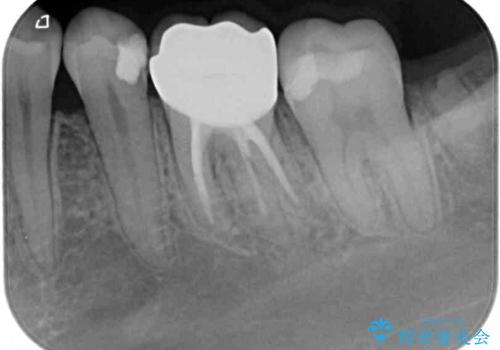

- 処置が必要と言われていたものの、長い間放置していた奥歯の治療を希望して来院された患者様です。

一番奥の歯は詰め物が脱離しており、仮詰め材が詰まっており、手前の歯は根管治療後に樹脂で固めたままの状態でした。

手前の歯を仮歯に置き換えるとともに、一番奥の歯のむし歯治療を行うこととしました。